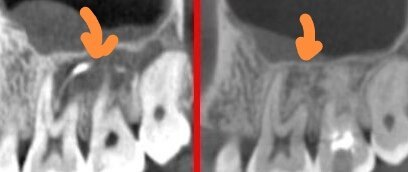

臨床上,經常會遇到根尖“囊腫”的患者。所謂的根尖“囊腫”,大多數情況都是X片(CT)上發(fā)現(xiàn)根尖陰影偏大,醫(yī)生告知患者是“囊腫”。為什么“囊腫”打隱號呢?因為病理才是診斷囊腫的金標準,有病理結果之前只能叫“囊腫”。對于根尖“囊腫”的治療方案,包括根管(再)治療、根尖手術、拔牙。如何選擇呢?根管(再)治療創(chuàng)傷性小,成功率偏低(低于五成);根尖手術創(chuàng)傷性大,成功率偏高(接近九成)。拔牙當然囊腫大概率就好了,但損失一顆牙。另外“囊腫”范圍越大,任何治療的成功率都會下降。所以目前單根牙根尖“囊腫”根管治療后根尖手術偏多。磨牙由于牙根多,磨牙的囊腫手術難度及風險很大,所以許多醫(yī)生對于磨牙囊腫的態(tài)度是拔牙。(至于磨牙囊腫是否手術,患者要問接診醫(yī)生他自己做不做,而不是只提一個方向但醫(yī)生自己不做)有些人患牙頸部剩余牙槽骨極窄(0.5mm左右),根尖手術極易導致此處牙槽骨吸收而失敗??傆腥藨峙率中g,更不想拔牙。有沒有可能用非手術的方法治療所謂的面積大些的根尖“囊腫”呢?個人近幾年做了一些嘗試。根尖囊腫由感染而來,根管治療只清潔處理根管內的感染,對于根尖囊腫的根外感染影響有限,如果根管內封藥時采用有明顯殺菌作用的材料(國家藥品監(jiān)督管理局目前不允許根管內用抗生素類藥物),也許會對根尖“囊腫”有治療作用。目前兒童口腔的根管治療材料是國藥局批準的,一般也用于成人某些情況短期封藥的并有明顯殺菌作用的材料。采用這種合法合規(guī)的材料,在適當時機輔助根管治療,目前3年左右的效果肯定。下圖是磨牙2年效果,“囊腫”愈合。下圖是累及多顆前牙的“囊腫”希望對需要的患者有所幫助。